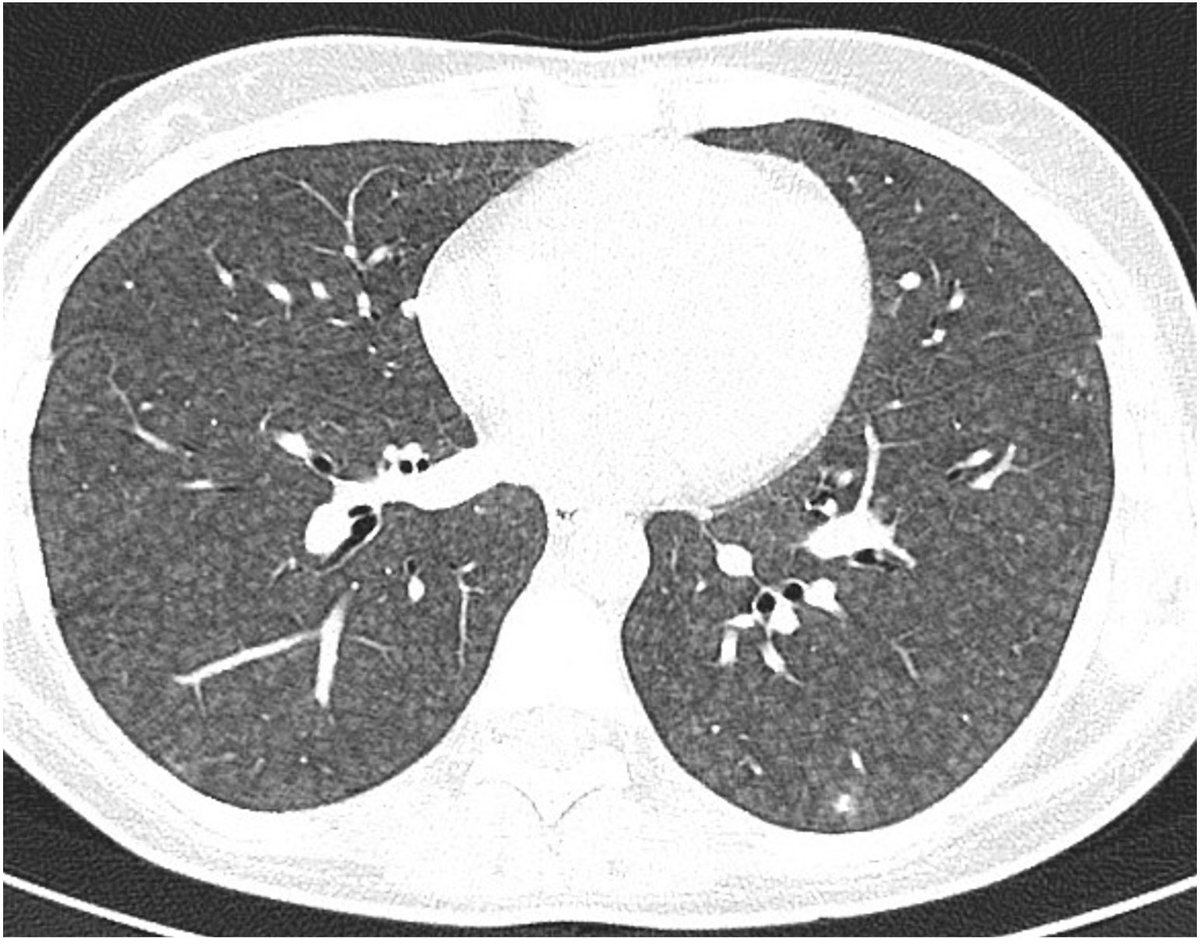

Hypersensitivity pneumonitis HP is not uncommon even if absent exposure history. Newly classified into non fibrotic and fibrotic by ATS/JRS/ALAT 2020. Each subclassified into typical and compatible. Indeterminate for HP confined for fibrotic type.

HRCT plays important role in diagnosis of HP and surgical biopsy could be avoided in management. Proper interpretation requires familiarity of HP features according to the new classification, typical or compatible or indeterminate for HP

Typical HP either fibrotic or not has 2 presentations. Profuse centrilobular nodules of ground glass density and three density sign (formerly headcheese sign) with bilateral lobular air trapping in 3 lobes at least, in case of absent features suggesting alternative diagnosis